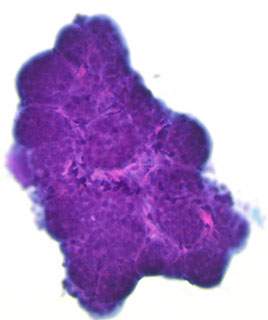

Mucinous (colloid) Carcinoma

“Islands of tumor cells floating in a sea of mucus”

The smear is relatively cellular with tumor cells arranged in cohesive sheets, balls, acini, strips of cells or singly dispersed

The nuclei show minimal atypia and are fairly uniform with fine chromatin and inconspicuous nucleoli

The backround mucus is pale blue to pink in Pap stain and metachromatic in Romanovsky stain.

The FNA biopsy obtains grossly recognizable mucus. The cytoplasm is delicate and may show red neurosecretory granules (best seen in Romanovsky stain)

Branching capillaries and psammoma bodies may be seen

Necrosis does not occur in pure mucinous carcinoma